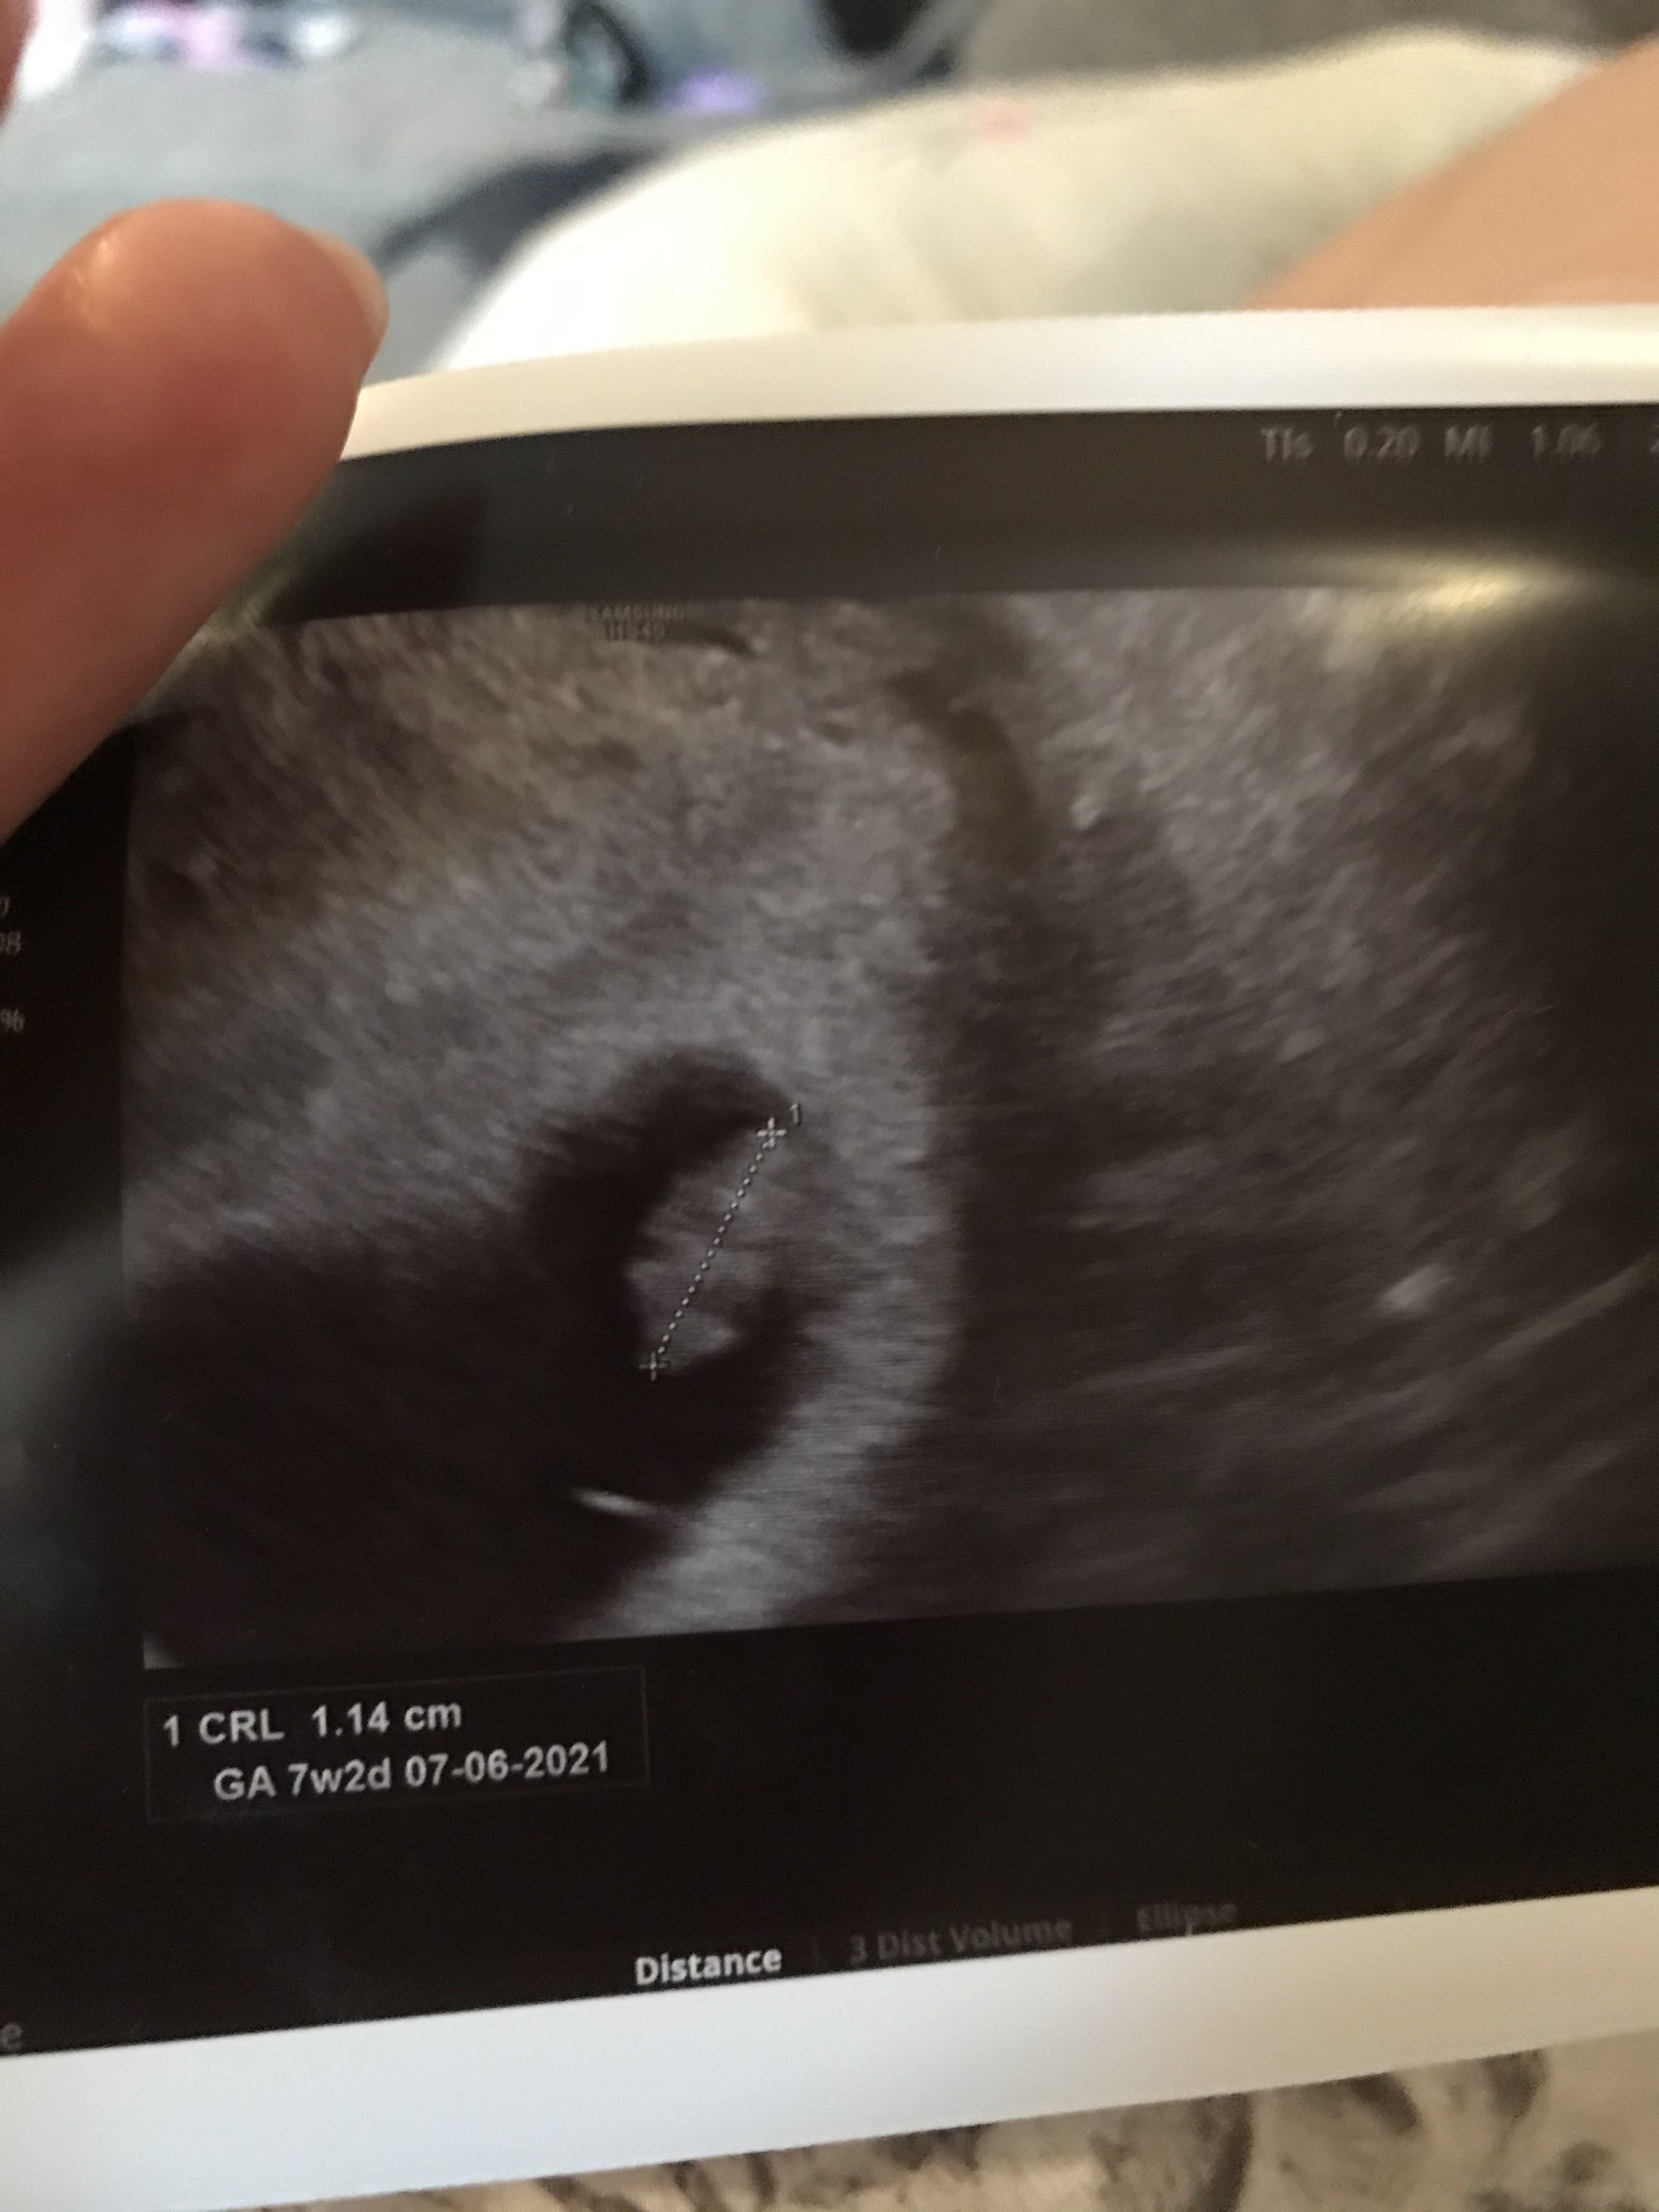

Teraz widzę usg ❤ jako duzy maluch ❤❤Jestem po wizycie- dzisiaj 7+2 był zarodek i widziałam pięknie bijące serduszko

plamienia mogły być spowodowane stresem i nerwami. Dostałam duphaston i luteinęZobacz załącznik 1191045